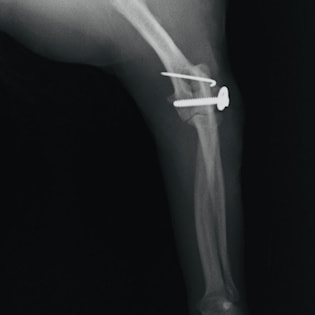

症例3:キルシュナーワイヤーのピンニングによる整復

ペルシャ猫 11ヶ月齢 雄

他院にて左大腿骨遠位の成長板骨折(salter-harrisⅠ型)が認められており、治療相談を目的として来院。当院にて、キルシュナーワイヤーを用いたピンニングにより骨折部位の整復を行いました。術後の経過は良好で、現在も経過観察中です。

術前レントゲン

術後レントゲン

Arthrex社のターゲティングデバイスを用いてピンニングの位置を調整することで、確実な固定を行っています。当院ではこの手術器具以外にも、人の手術にも使用される様々な器具を導入し、手術精度を高め、また医療メーカーと新しい器具の開発、試作にも取り組んでおります。